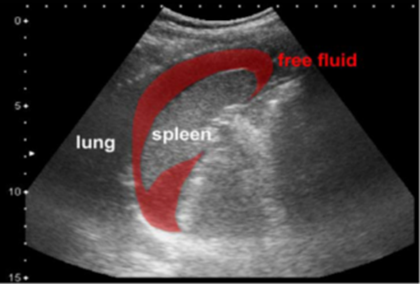

This system addresses a critical gap in battlefield medicine by delivering instant volumetric 3D/4D imaging with AI-guided eFAST for detecting non-compressible torso hemorrhage (NCTH). Using a planar matrix-array (32x32) transducer and GPU-accelerated beamforming, it enables real-time imaging at ~20 volumes per second with guided acquisition and automated interpretation.

- On-device AI with guided prompts and automated interpretation for reliable eFAST workflows.

- Automated diagnostic tool (Morison’s pouch) — TRL 6